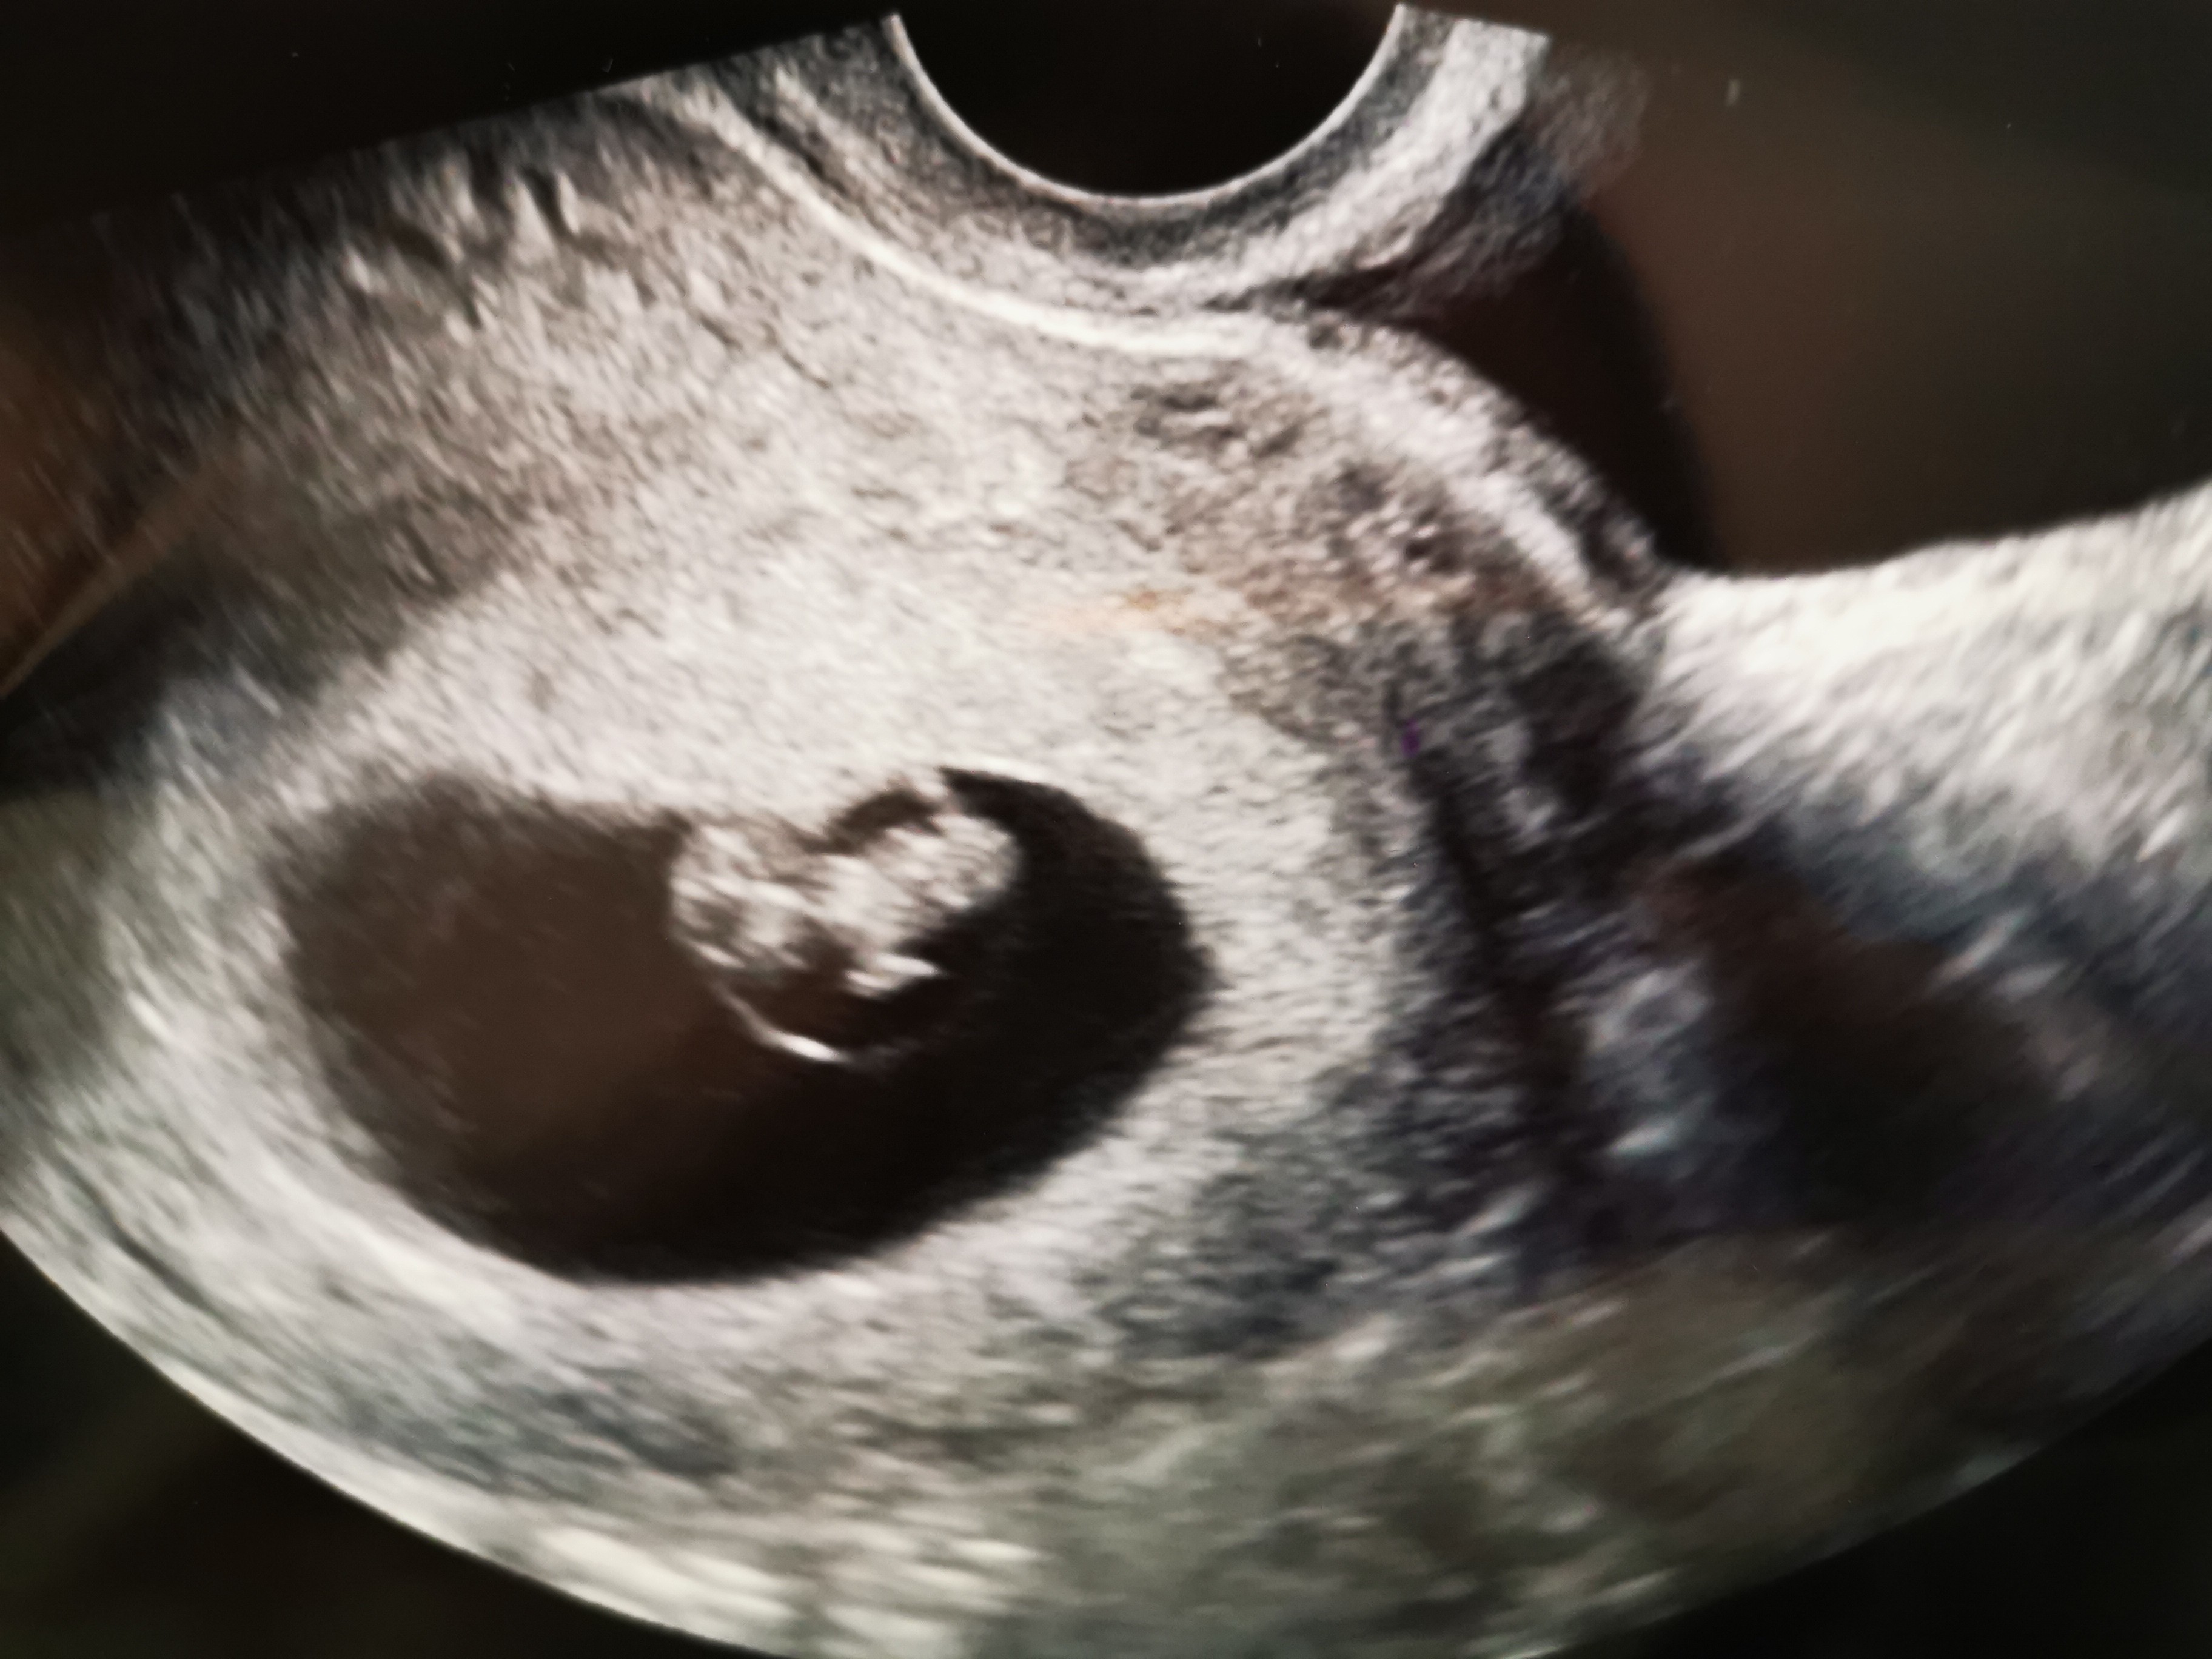

Ciąża starsza o 4 dni wg USG, czyli dziś 8t0d, ❤️ bije jak dzwon😊

Za dodatkowe 10£ kupiliśmy link do video z całego USG i czuję że dziś będę zapętlać cały dzień😍

• IMG_20201104_154411.jpg

IMG_20201104_154411.jpg

1,1 MB · Wyświetleń: 114